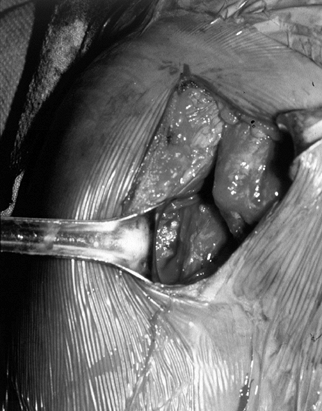

Figure 79.12. Incision parallel to the acromion to expose a rotator cuff tear. Arm is still suspended from overhead traction. -

With the patient in the same position, make a strap incision paralleling the lateral edge of the acromion (Fig. 79.12).

middle one third of the deltoid) (Fig. 79.13). Insert a smooth, self-retaining retractor to inspect the rotator cuff (Fig. 79.14). Gentle traction on the humerus often improves visualization.

Figure 79.13.

Raphe between the anterior and middle heads of a deltoid. After

splitting raphe, a self-retaining retractor allows more than adequate

exposure of the torn supraspinatus.

Figure 79.14. View of the torn rotator cuff using mini–open incision. -